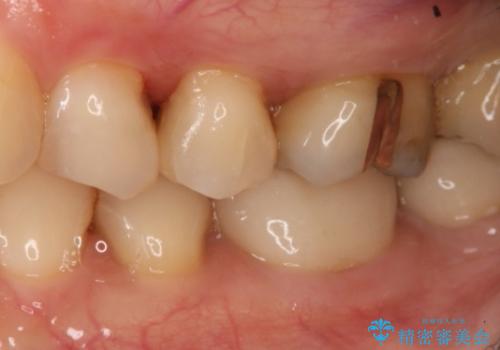

- 左上奥歯の銀歯のやり変えを希望された患者様です。

白くしたいとの事だったので形態・切削量を考慮し、セラミックインレーでの治療を計画しました。

保険材料と比較し、セラミックは劣化しない材料なので二次的な虫歯を防ぐことが出来ます。